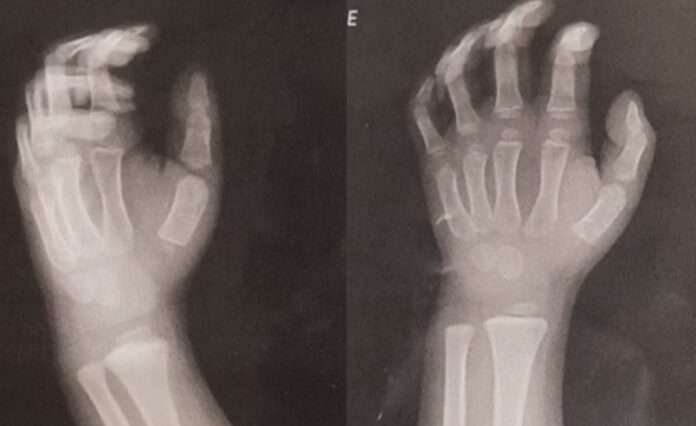

A família percebeu o machucado ao buscar o menino no dia 28 de maio e o levou imediatamente a uma Unidade de Pronto Atendimento (UPA), onde exames confirmaram o deslocamento do osso.